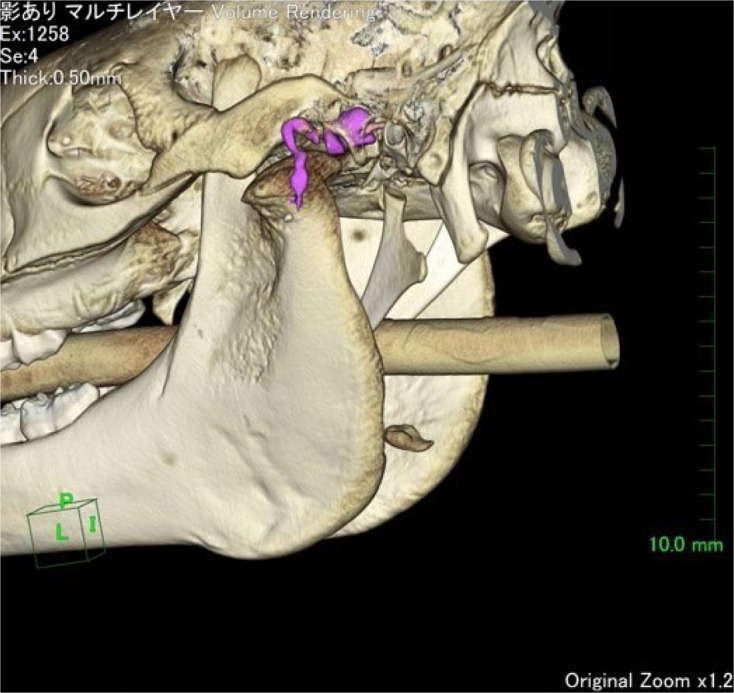

Computed tomography (CT) offers high-resolution, three-dimensional imaging, making it particularly valuable for assessing complex structures, such as the head, especially when conventional radiography and endoscopy are insufficient for a definitive diagnosis. Herein, we present two cases of equine cranial disorders resulting from congenital malformations. In case 1, which had a dentigerous cyst, CT images confirmed the location of the ectopic tooth within the skull and a detailed fistula tube. In case 2, which had temporohyoid osteoarthropathy, CT examination revealed that the stylohyoid bone was malformed, and the inner ear was presumed to be filled with soft tissue with calcification. The information obtained by CT was invaluable, as it allowed for accurate diagnosis and precise surgical planning.

计算机断层扫描(CT)提供高分辨率的三维成像,使其在评估复杂结构(如头部)时特别有价值,特别是当传统的x线摄影和内窥镜检查不足以进行明确诊断时。在此,我们提出了两个病例马颅疾病导致先天性畸形。病例1为含牙囊肿,CT图像确认了异位牙在颅骨内的位置和详细的瘘管。病例2为颞舌骨骨关节病,CT检查提示茎突舌骨畸形,推测内耳充盈有钙化软组织。CT所获得的信息是非常宝贵的,因为它允许准确的诊断和精确的手术计划。